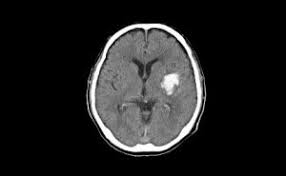

- 뇌내출혈(Intracerebral Hemorrhage): 뇌 실질 내에서 출혈 발생

뇌출혈과 뇌경색은 모두 뇌졸중의 한 종류이며 증상이 유사하지만, 치료 방법과 예후가 다릅니다. 다음은 뇌졸중, 뇌출혈, 뇌경색의 차이점을 비교한 표입니다.

출혈량과 위치, 초기 대응 시점에 따라 회복 가능성이 크게 달라집니다.

뇌간이나 대뇌 심부에 출혈이 생기면 생존율이 낮고, 운동 피질 부위에 출혈이 생기면 마비가 남을 수 있습니다.